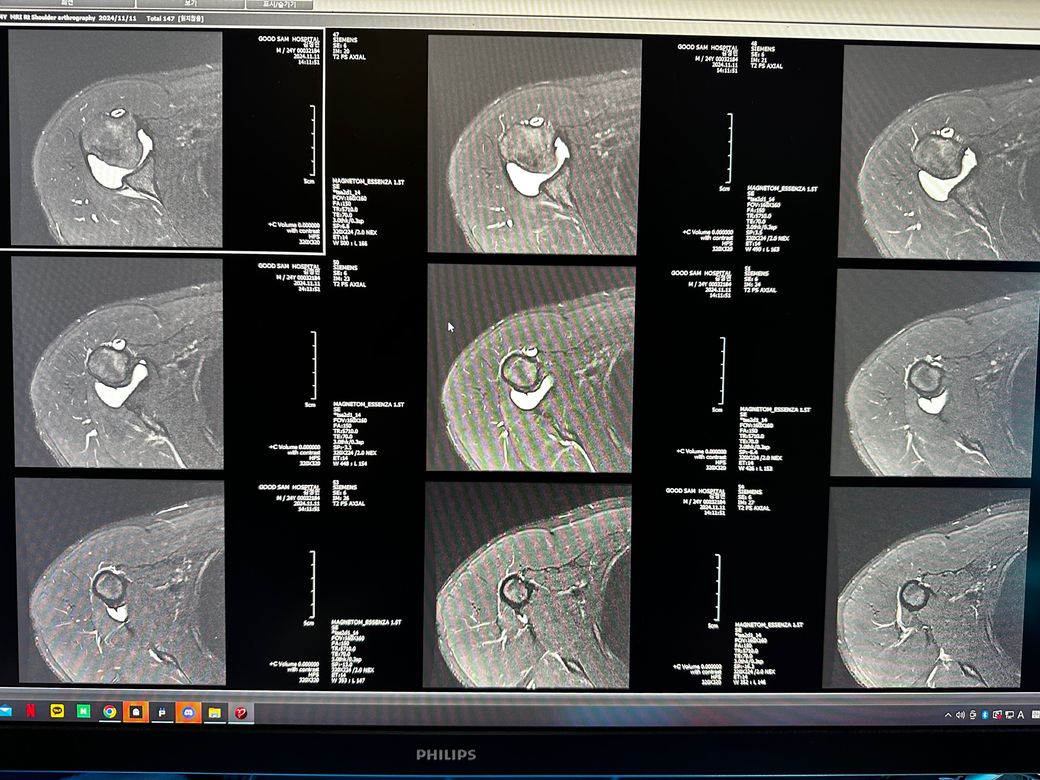

오른쪽어깨 관절mri좀 봐주세요 사진첨부입니다

오룬쪽어깨관절 엠알아이 결과좀 봐주세요

오른쪽어깨관절부분입니다

관절입니다

• 7번 째 사진

• 8번 째 사진

• 9번 째 사진

조영제가 들어간 것으로 보이며, "회전근개(특히 극상근) 파열이나 큰 손상은 뚜렷하게 보이지 않는 편"입니다.

관절와순(Labrum) 주변에 조영제가 퍼져 보이지만, "명확한 파열 소견은 사진만으로 단정 어렵고 경미한 손상.염증 가능성"은 있습니다.

관절 안쪽에 "약한 염증/활액 증가"는 있어 보이며, 충돌증후군 초기 형태 가능성이 있습니다.